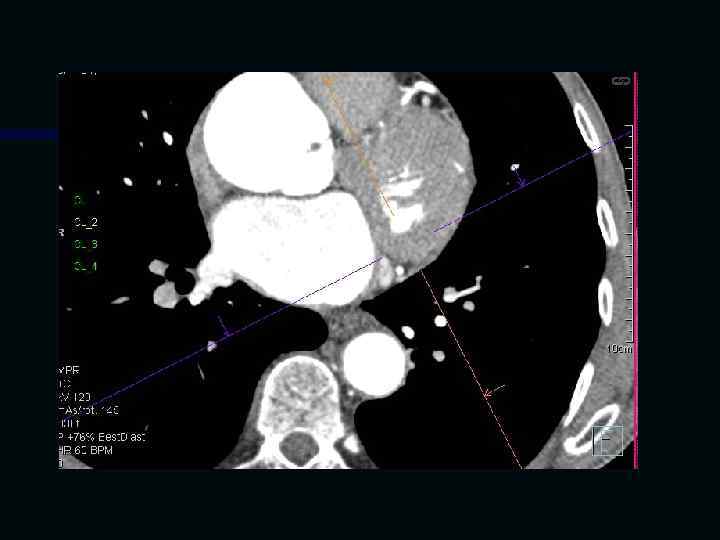

Исследование сосудов грудной клетки